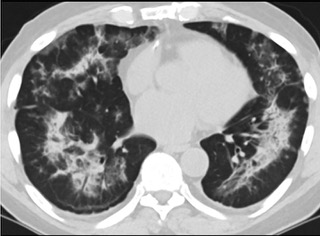

疑点一,电子烟患者的CT影像和临床表现并不具有特异性。所谓美国电子肺炎患者,其实是对没有其他合理诊断证据、吸食电子烟肺炎患者的统称。这些患者在病发前90天内吸食了电子烟,尤其值得注意的是,部分患者的CT影像特征和临床表现与病毒性肺炎患者极其相似。

中、下肺轴位CT平扫显示毛玻璃样混浊伴胸膜下保留。(同一病人CT影像)

中、下肺轴位CT平扫显示毛玻璃样混浊伴胸膜下保留(箭头)。(同一病人CT影像)

6天后的轴向CT平扫图像显示毛玻璃影变为实变和轻度结构扭曲。(同一病人CT影像)

16位被文献报道为电子烟肺炎的患者被专家判定为“病毒性感染”,即有可能是新冠肺炎的“疑诊患者”,其中更有5位临床症状和治疗情况相对完整的患者被判定为“中度可疑”。因此在2019年美国报道的电子烟肺炎中存在病毒性感染的病例,而且不排除美国电子烟肺炎中存在新冠肺炎的可能性。